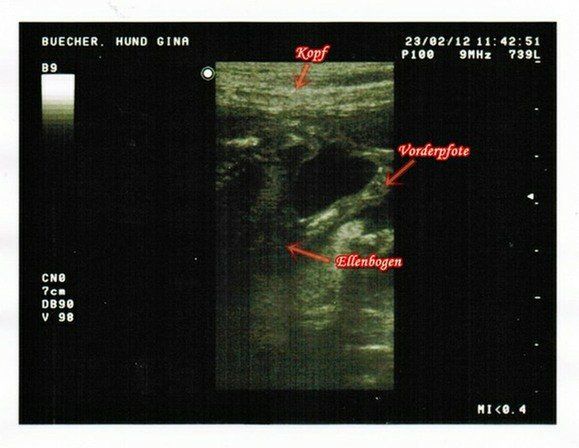

Die Zeit vergeht wie im Flug. In Ginas Bauch tobt bereits der Bär. Mit ca. 8 cm sind die Kleinen

schon so groß, dass auf das Ultraschallbild nur mehr Ausschnitte passen.

Die Herzen schlagen kräftig, die Leber ist größentechnisch richtig dominant, auch eine Darmschlinge konnten wir erkennen.

Viele Pfoten strampeln und treten … der Platz wird langsam weniger.